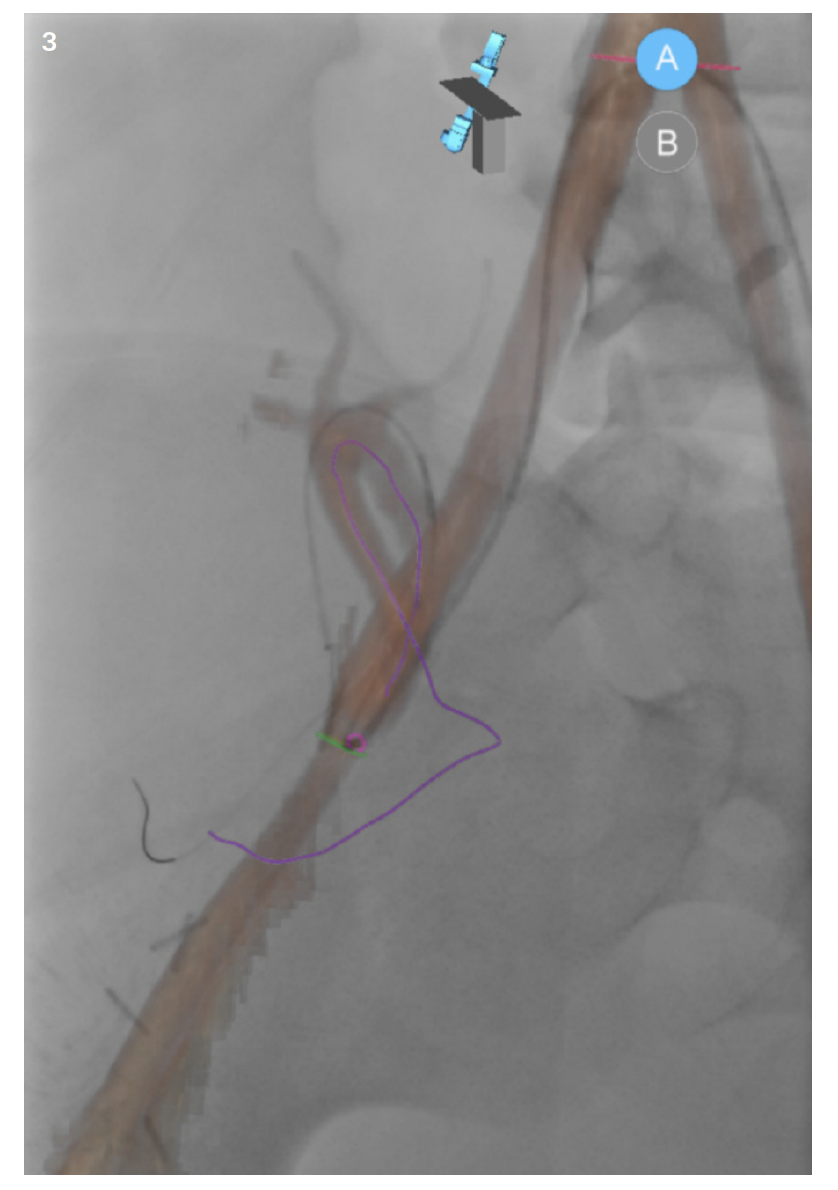

In pediatrics, MR and CT datasets are mainly used for fusion to assist with intraprocedural guidance and road mapping. As with most things in pediatrics, its use is currently limited. It is, however, an area of interest that is growing among the community. Sometimes patient vascular anatomy is complex; other times, patient size makes navigating even normal anatomy difficult. Though most interventionalists would be able to perform a complicated case without assistance, the datasets have potential to help decrease patient radiation and contrast dose in the hands of even the most skilled users. This may be able to be accomplished through use of the patient’s prior cross-sectional imaging to create 3D roadmaps on the day of treatment. While it may not be a “perfect” one-to-one recreation of the patient’s anatomy, the roadmap created and overlaid on live fluoroscopy is often more than sufficient (Figure 1). In complex cases, the roadmap created will at the very least give the interventionalist a better approximation of where a tortuous vessel’s origin might be in the 3D space (Figure 2). And if the interventionalist has a better idea of the vessel origin, they may be able to select it faster, thus limiting patient radiation and contrast dose. And while the same software can be used for even more advanced techniques such as organ segmenting, it is straightforward to use. It doesn’t matter how useful or “nifty” you think something is if it is unreliable and cumbersome to implement. Once the interventionalist understands Siemens’ simple and intuitive workflow, use of prior imaging in this manner is something that can easily be done with little effort and time. The other thing to keep in mind is with the simplified workflow; if whatever overlay was created using the patient’s prior imaging is not helpful or is a hinderance, it can easily be turned off. While it may seem counterintuitive, the ability to easily turn off an advanced feature if it is not serving its purpose is just as important as to not waste time in the suite doing unnecessary troubleshooting.